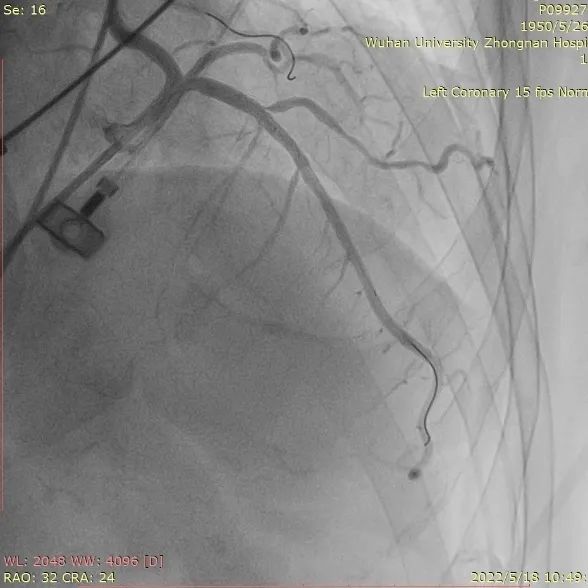

1. 患者前降支中段重度狭窄,先行左冠PCI术后,进行TAVR手术;

取平卧位,行右侧股动脉穿刺,置入6F鞘管,注入7000U肝素,分别送EBU3.75、EBU4.0、JL4指引导管均未能到达左冠口,EBU4.0塑型后成功达到左冠口,送VT导丝至前降支远端,送BMW导丝至回旋支远端,送2.0*20mm双导丝球囊于前降支近段狭窄处充分预扩张;送波科3.0*24mmDES一枚至前降支中段病变处,精准定位后释放,分别送3.5*16mm乳突球囊、3.0*15mmNC球囊至支架内修饰扩张。复查造影示支架膨胀良好,撤除鞘管,常规加压包扎,注意有无出血及高迷走反射。

冠造提示左冠前降支狭窄处

PCI后血流通畅

重度主动脉瓣反流可以导致冠脉血流灌注减少,从而诱发心绞痛。该患者术前同时合并前降支重度狭窄,因此,在经心尖TAVR前可以先对上述狭窄部位行PCI治疗,这样可以充分改善TAVR术后的心肌供血,在最大程度上使患者获益经心尖TAVR的治疗。J-Valve瓣膜属于短支架瓣膜,结合顶端独有的波浪形设计,降低了冠脉风险,同时为日后老年人的PCI治疗留下了一个生命通道。